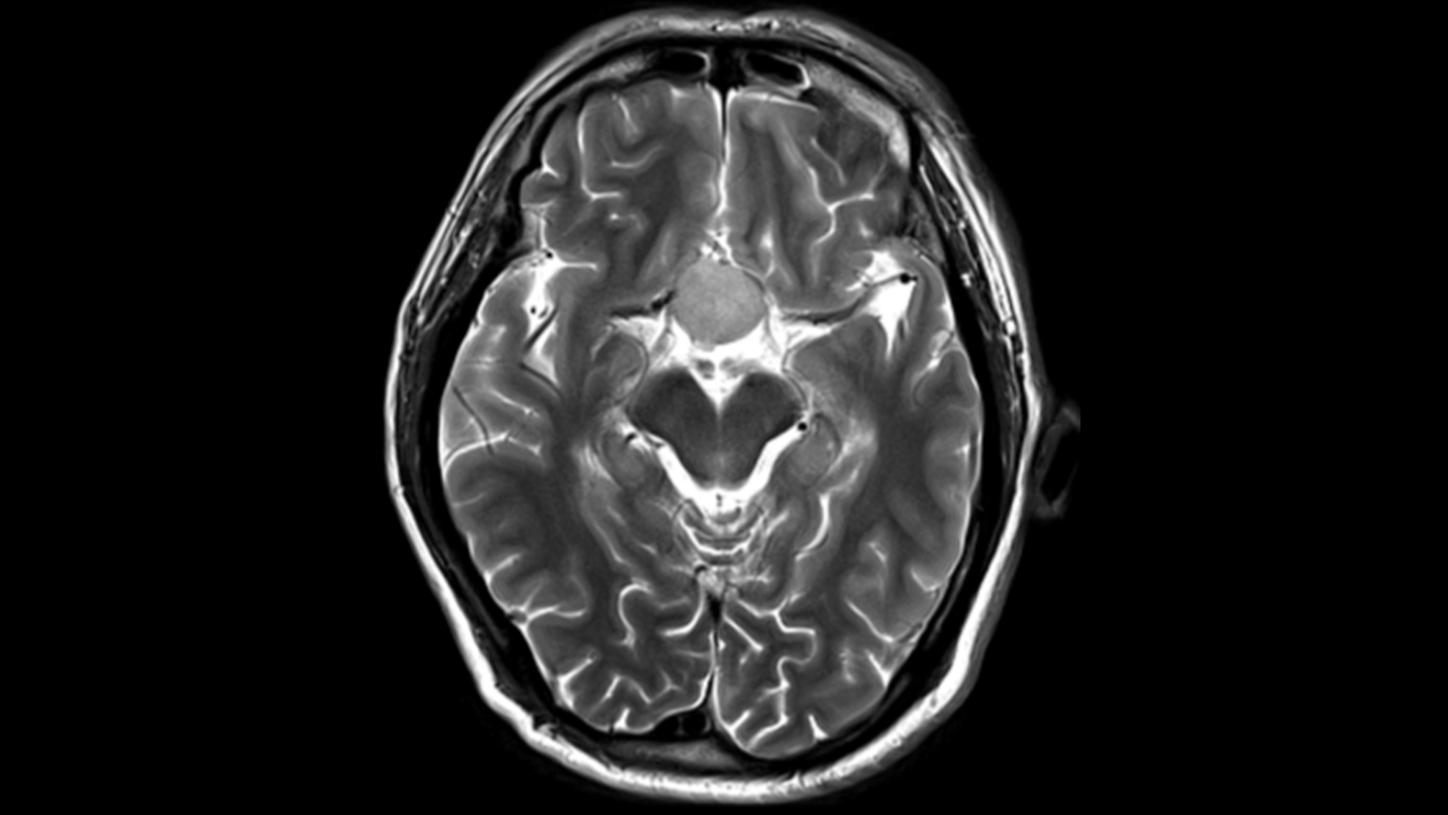

Key investigation areas for MRI are soft tissue areas like brain, abdomen, vessels, ligaments, cartilages or muscles.

Fig.1: Courtesy of Tongji Hospital, Wuhan, China